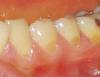

bojun Опубликовано 26 октября, 2007 Поделиться Опубликовано 26 октября, 2007 Зашла к врачу (думала, что это - парадонтит) - "успокоил": "нет, только дефект эмали, надо пломбировать, но можо и так ходить..." Никакой там реминирализующей терапии, никаких рекоммендаций, конкретных диагнозов... (клиновидный? эрозия?... еще что? ) Скажите, пожалуйста, что это у меня? на какой стадии? что делать? - реминирализация или уже пломбировать?а пломбы при таких делах обыкновенные? а это дело под пломбой дальше расти не будет? я вот боюсь - как же мне будут это дело "сверлить" - еще больше эмаль повредят?... И что, кислого ничего не есть? лимоны, гранаты, сухое вино - забыть, да? или если сразу полоскать, то можно? Спасибо, что есть такой ваш форум, где, надеюсь, получу квалифицированный ответ и совет! Ссылка на комментарий

Снежана Опубликовано 27 октября, 2007 Поделиться Опубликовано 27 октября, 2007 Зашла к врачу (думала, что это - парадонтит) - "успокоил": "нет, только дефект эмали, надо пломбировать, но можо и так ходить..." Никакой там реминирализующей терапии, никаких рекоммендаций, конкретных диагнозов... (клиновидный? эрозия?... еще что? ) Скажите, пожалуйста, что это у меня? на какой стадии? что делать? - реминирализация или уже пломбировать? а пломбы при таких делах обыкновенные? а это дело под пломбой дальше расти не будет? я вот боюсь - как же мне будут это дело "сверлить" - еще больше эмаль повредят?... И что, кислого ничего не есть? лимоны, гранаты, сухое вино - забыть, да? или если сразу полоскать, то можно? Спасибо, что есть такой ваш форум, где, надеюсь, получу квалифицированный ответ и совет! Это у вас клиновидные дефекты, лучше их запломбировать, т.к. эмаль в области дефектов уже стерлась и дырочки будут постепенно увеличиваться. Пользуйтесь мягкой зубной щеткой и пастой для зубов с повышенной чувствительностью, при чистке зубов исключите горизонтальные движения зубной щеткой. От лимонов лучше отказаться. Пломбы при любых делах лучше качественные светоотверждаемые. Ссылка на комментарий

NataLee Опубликовано 27 октября, 2007 Поделиться Опубликовано 27 октября, 2007 (изменено) Док, просьба перенести тему в "наш" раздел, дабы мы могли пообщаться с доктором. А то здесь как-то не комфортно Пока тема ещё здесь... парочку слов скажу. Надо найти причину этих клиновидных дефектов. А причина в данном случае, как мне представляется - неправильный прикус. Прежде чем что-то делать, нужна консультация ортодонта (и в оптимале - исправление прикуса). Иначе и пломбирование, и пасты бесполезны. После получения резюме ортодонта, если дело всё-таки в прикусе - пломбирование дефектов и ортодонтическое лечение. Касательно использования пасты для снижения чувствительности: на семинаре компании "GlaxoSmithKline" (Сенсодин) нам давали такую схему: 1 неделю - ежедневно, далее 2-3 раза в неделю. Изменено 27 октября, 2007 пользователем NataLee Ссылка на комментарий

Мартовский Опубликовано 27 октября, 2007 Поделиться Опубликовано 27 октября, 2007 В общем смысл ответа такой - не только ваш врач затрудняется с постановкой точного диагноза. Если это эрозия, то реставрация даст нужный эффект. Если клиновидный дефект, то эффект будет временный, нужно искать причину его возникновения, а она в перегрузке зубов, которая может возникнуть из-за прикуса, заболеваний парадонта. Коллеги, я все правильно перечислил? Ссылка на комментарий

bojun Опубликовано 28 октября, 2007 Автор Поделиться Опубликовано 28 октября, 2007 большое спасибо всем! начала пользоваться пастой biocalcium (с гидроксиапатитом, натуральным биоактивным кальциеми бикарбонатом натрия) и Лакалют... и еще полоскатель с фтором , мелиссой, ромашкой и шалфеем... правильно? (правда, купила все это до тоого, как прочитала ваши рекоммендации. ) пойду схожу к другому врачу завтра... Начет причин моего КД скажу вот что:- во-первых, еще в детстве говорили, что прикус у меня не правильный (верхняя челюсть слегка вперед), но отклонение маленькое, видимо, поэтому с ним не боролись... Это что, сейчас брэкеты надевать, да? лучше бы в детстве поносила... - у меня в последние пару лет напряженный период в жизни... в карьере... сплю плохо, просыпаюсь - челюсти болят - зубы даже во сне сжимаю... муж говорит, даже скрежещу иногда. Может, в этом и причина? Но почему тогда дефект у десны? - пардон за глупый вопрос - а не на верхней поверхности зуба? Прикус у меня не до такой степени неправильный, чтобы верхние зубы доставали до основания нижних!...Еще раз спасибо всем! И где же вы водитесь, врачи, любящие свою работу?... Только в Росии, что ли?... Ссылка на комментарий

Штаматолог Опубликовано 28 октября, 2007 Поделиться Опубликовано 28 октября, 2007 большое спасибо всем! начала пользоваться пастой biocalcium (с гидроксиапатитом, натуральным биоактивным кальциеми бикарбонатом натрия) и Лакалют... и еще полоскатель с фтором , мелиссой, ромашкой и шалфеем... правильно? (правда, купила все это до тоого, как прочитала ваши рекоммендации. ) пойду схожу к другому врачу завтра... Начет причин моего КД скажу вот что: - во-первых, еще в детстве говорили, что прикус у меня не правильный (верхняя челюсть слегка вперед), но отклонение маленькое, видимо, поэтому с ним не боролись... Это что, сейчас брэкеты надевать, да? лучше бы в детстве поносила... - у меня в последние пару лет напряженный период в жизни... в карьере... сплю плохо, просыпаюсь - челюсти болят - зубы даже во сне сжимаю... муж говорит, даже скрежещу иногда. Может, в этом и причина? Но почему тогда дефект у десны? - пардон за глупый вопрос - а не на верхней поверхности зуба? Прикус у меня не до такой степени неправильный, чтобы верхние зубы доставали до основания нижних!... Еще раз спасибо всем! И где же вы водитесь, врачи, любящие свою работу?... Только в Росии, что ли?... Если у Вас неправильный прикус и бруксизм - Вам прямая дорога к ортодонту, иначе пломбирование ничего не даст - через некоторое время все повываливается. Исправлять прикус и каппу на ночь. Ссылка на комментарий

Снежана Опубликовано 28 октября, 2007 Поделиться Опубликовано 28 октября, 2007 Этиология клиновидных дефектов до конца не изучена, есть механическая теория возникновения кл. дефектов и эрозии эмали, а так-же в возникновении эрозий может играть роль гиперфункция щитовидной железы (есть смысл сдать анализы на гормоны). Дефекты тв. тканей при эрозии симметричны (т.е. с 2-х сторон), при клиновидном дефекте чаще либо поражена одна сторона (у правшей левая), либо с одной стороны дефекты более выражены, чем с другой. Ссылка на комментарий